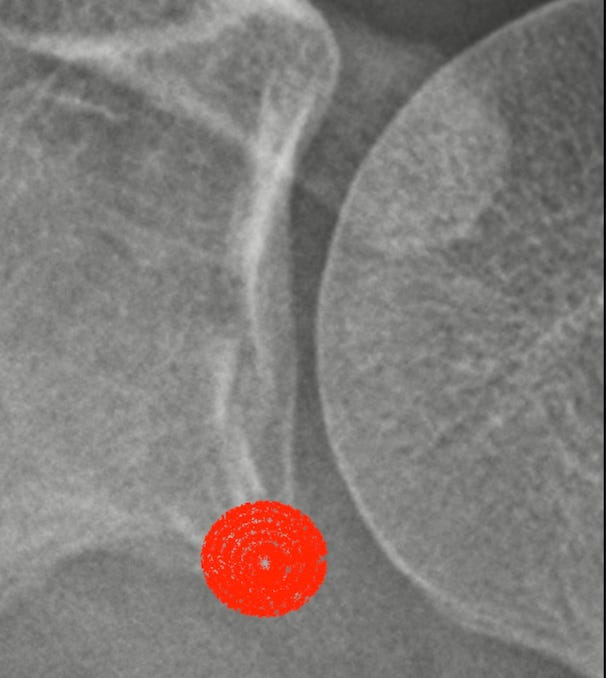

A little over two weeks ago, as I was taking a walk over lunch to settle my mind from a chaotic workday I encountered a low hanging drone. It seemed to be following me, hanging low and pacing me just above or just behind me. It caught my attention and focus while I hit the sidewalk wrong. Feeling the fall coming, I gave those around my best Three Stooges. Flinging and flailing my arms and legs trying to re-center and stand only to miss and fall straight onto my shoulder with all 175 pounds of me on the concrete sidewalk. I heard the familiar crunch. I laid for a moment to catch my breath and tried to move my arm while making my way back to my feet while doing my well practiced tests in search for a break. Uncertain I went to urgent care where the first pass of the X-rays read as no break. I later received a call that after further review I had in fact fractured my shoulder socket. More than that, an uncommon and hard to heal fracture that requires three weeks of immobilization.

Immobilization requires that I have my arm in a sling near my body. No repeated motion, no weight bearing, no stretching, no typing, etc. All forcing me to rethink how I get the basics done and foster rest and convalescing. This fracture is 1mm away from being a bigger problem that could require surgery. The nod toward my life’s pattern reminding me that a second break is the width of a grain of sand away.